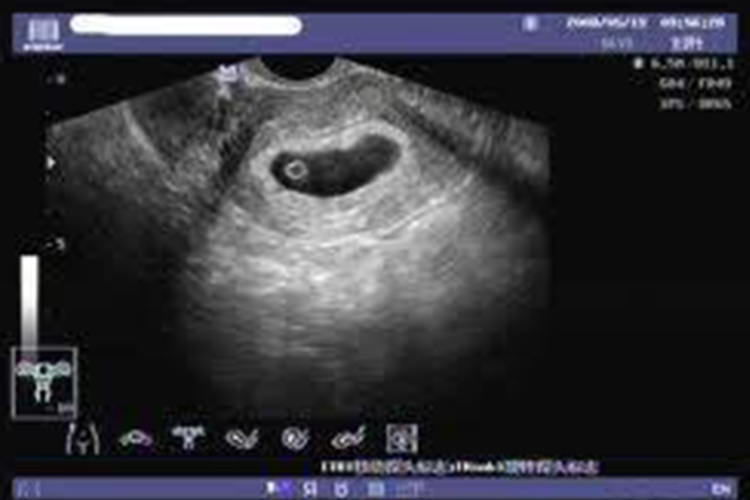

妊娠囊是早期妊娠标志物,一般可在停经35天左右,经阴道超声,在宫腔内可见到圆形或椭圆形的妊娠囊。它是由绒毛膜形成的环形结构,环内为无回声暗区,外围为强回声环,强回声环外是低回声环,即双环征,是早期妊娠囊在B超下的重要特征。一般在妊娠第5-6周,可见胚芽和胎心搏动,为规律性闪烁光点。随孕周增大,妊娠囊逐渐增大,至妊娠12-13周左右,羊膜囊充满子宫腔,并与子宫壁重合,不再显示妊娠囊。